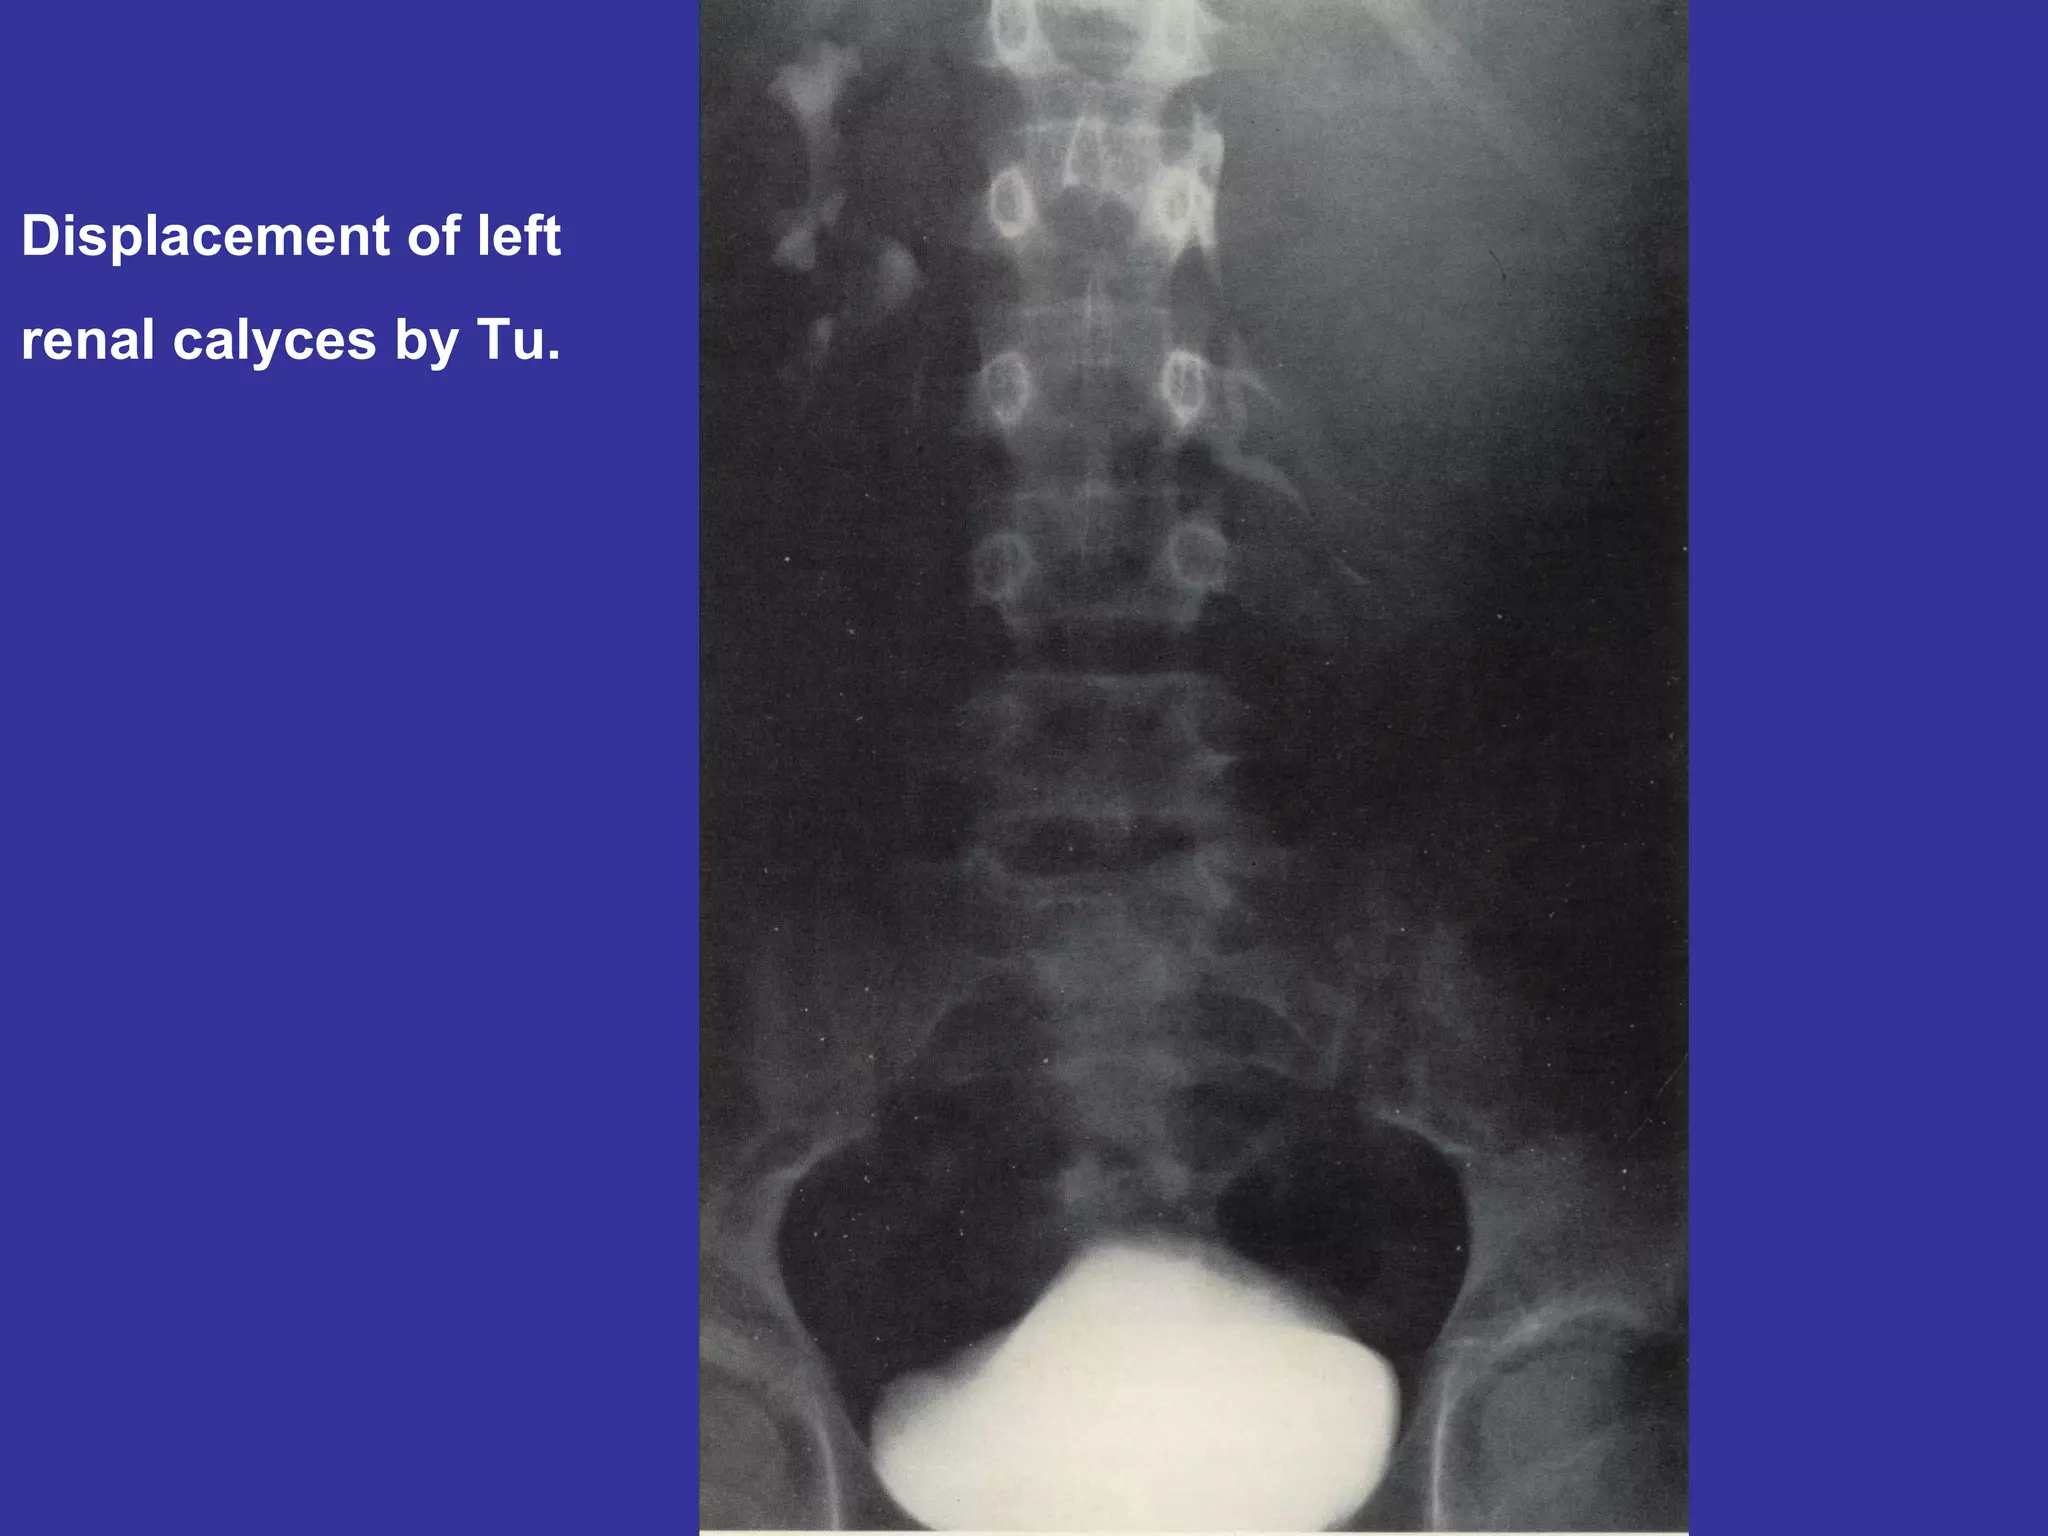

WILMS TUMOR (Nephroblastoma) Malignant tumor of the kidney in the pediatric age.  Epidemiology: 5% of all childhood cancer 50% occurs under 3 years old Peak age:  2-4 years Higher incidence in Black female children Associated to congenital anomalies Genetics: 15-20% are hereditary in origin Familial cases are often bilateral and occurring at earlier age S/S:  Fever, anorexia, hematuria, abdominal pain/distention, anemia,  HTN- 60%, due to obstruction of renal art.  P.E.: Abd.  mass  extending from flank toward midline abd.  Is unilateral.  Associated with aniridia, cryptorchidism, horseshoe kidney  Metastasis to:  Lung, liver, bone, brain

LAB:   CBC, Lytes, Urine analysis (micro/macro hematuria), liver/kidney profile Biopsy and staging of tumor (prognosis depend on staging and Bx.) Imaging:  U/S of abdomen CT of abdomen Chest X-Ray: R/O chest metastasis Dx:  CT and Bx TX:   Surgery- Nephrectomy, sometimes followed by Chemo and Radiation Radiation: for stages III/IV or pulmonary metastasis Chemo: Stages I/II- Vincristine / actinomycin D, every 3 weeks for 6 M Stages III/IV- Vincristine, AMD, doxorubicin for 6-15 months.

STAGING: Stage I-  Tu. restricted to one kidney and completely resected.  Renal capsule intact Stage II-  Tumor extends beyond the kidney but is completely excised Stage III- Residual nonhematogenous tumor is confined to the Abd. Stage IV- Hematogenous spread to lungs and liver Stage V-  Bilateral disease Prognosis:   Favorable:   Stage I/II- more than 90% cured Age at presentation less than 24 months Tumor weight less than 250g Poor:   Anaplastic pathology Lymph node involvement Distant metastasis

Displacement of left renal calyces by Tu.

WILMS TUMOR (Nephroblastoma)Malignant tumor of the kidney in the pediatric age. Epidemiology: 5% of all childhood cancer 50% occurs under 3 years old Peak age: 2-4 years Higher incidence in Black female children Associated to congenital anomalies Genetics: 15-20% are hereditary in origin Familial cases are often bilateral and occurring at earlier age S/S: Fever, anorexia, hematuria, abdominal pain/distention, anemia, HTN- 60%, due to obstruction of renal art. P.E.: Abd. mass extending from flank toward midline abd. Is unilateral. Associated with aniridia, cryptorchidism, horseshoe kidney Metastasis to: Lung, liver, bone, brain

Displacement of leftrenal calyces by Tu.